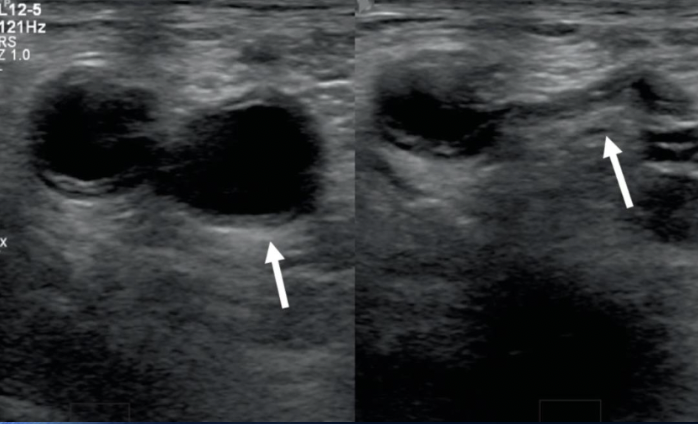

what is the arrow pointing to

Normal IVC (as it can be compressed)

Pathology?

DVT in the Common femoral vein